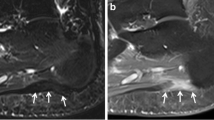

Out of the n = 60 initially included patients, n = 29 did not reveal bone marrow edema-like signal MRI findings at the Lisfranc joint and were excluded from the analysis of this study. Mean age was 68 years, standard deviation (SD) ± 19.5 years, median 67.7 years, IQR 24.8 years, range 23–99 years, 17 males, and 14 females. Imaging examples of precontrast STIR and postcontrast STIR are given in Fig. 1.

Obscured bone marrow edema-like signal on postcontrast STIR images. Precontrast STIR images of four different patients (A to D) with bone marrow edema-like signal at the Lisfranc joint (left) show signal suppression on postcontrast STIR images (right). A 1.5-T MRI of an 84-year-old male patient shows bone marrow edema-like signal at the base of the second metatarsal bone on precontrast STIR (left, white arrow). The signal intensity of bone marrow edema-like signal is reduced even below the adjacent normal appearing bone on the corresponding postcontrast STIR image (right, white arrow). B 1.5-T MRI of a 94-year-old male patient with bone marrow edema-like signal on both sides of the Lisfranc joint of the first ray (left, white arrow) on precontrast STIR with complete suppression of the signal on postcontrast STIR (right). C 3-T MRI of a 69-year-old female patient shows bone marrow edema-like signal with cystic changes at the Lisfranc joint of the second ray on precontrast STIR (left, white arrow) with nearly complete signal suppression on postcontrast STIR (right). Note the persisting high signal of the cystic changes on the postcontrast STIR image (white arrow). D 1.5-T MRI of a 37-year-old female patient with bone marrow edema-like signal at the base of the second metatarsal bone on precontrast STIR (left, white arrow) with complete signal suppression on the postcontrast STIR image (right)